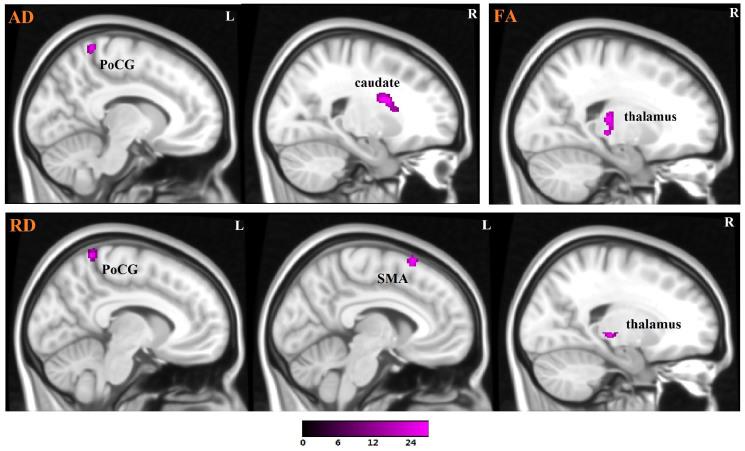

Previous research has demonstrated that there are specific white matter abnormalities in patients with attention deficit/hyperactivity disorder (ADHD). However, the results of these studies are not consistent, and one of the most important factors that affects the inconsistency of previous studies maybe the ADHD subtype. Different ADHD subtypes may have some overlapping microstructural damage, but they may also have unique microstructural abnormalities. The objective of this study was to investigate the microstructural abnormalities associated with two subtypes of ADHD: combined (ADHD-C) and inattentive (ADHD-I). Twenty-eight children with ADHD-C, 28 children with ADHD-I and 28 healthy children participated in this study. Fractional anisotropy (FA), radial diffusivity (RD) and axial diffusivity (AD) were used to analyze diffusion tensor imaging (DTI) data to provide specific information regarding abnormal brain areas. Our results demonstrated that ADHD-I is related to abnormalities in the temporo-occipital areas, while the combined subtype (ADHD-C) is related to abnormalities in the frontal-subcortical circuit, the fronto-limbic pathway, and the temporo-occipital areas. Moreover, an abnormality in the motor circuit may represent the main difference between the ADHD-I and ADHD-C subtypes.

先前的研究表明,注意缺陷多动障碍(ADHD)患者存在特定的白质异常。然而,这些研究的结果并不一致,影响先前研究不一致性的最重要因素之一可能是ADHD亚型。不同的ADHD亚型可能存在一些重叠的微观结构损伤,但也可能有独特的微观结构异常。本研究的目的是调查与ADHD的两种亚型相关的微观结构异常:混合型(ADHD-C)和注意力不集中型(ADHD-I)。28名ADHD-C儿童、28名ADHD-I儿童和28名健康儿童参与了本研究。采用分数各向异性(FA)、径向扩散率(RD)和轴向扩散率(AD)分析扩散张量成像(DTI)数据,以提供有关异常脑区的具体信息。我们的结果表明,ADHD-I与颞枕区异常有关,而混合型(ADHD-C)与额-皮质下环路、额-边缘通路和颞枕区异常有关。此外,运动环路异常可能是ADHD-I和ADHD-C亚型之间的主要差异。